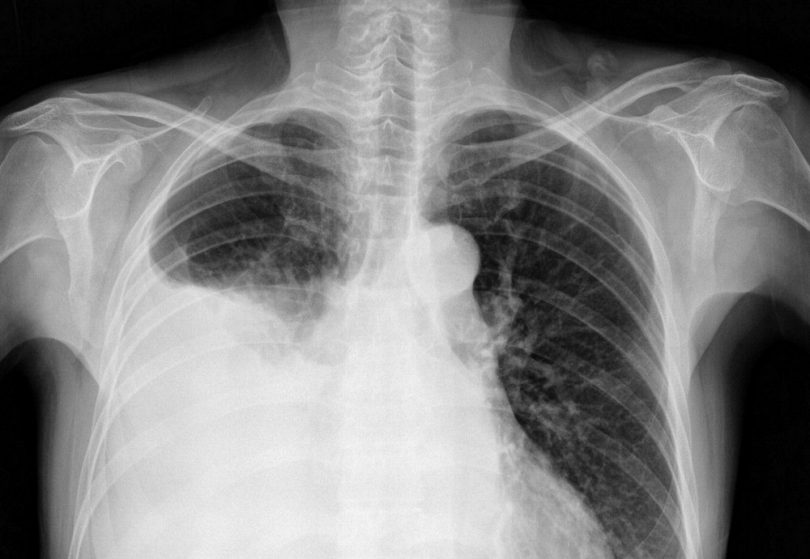

Как показывает медицинская практика, довольно часто врачи диагностируют у своих пациентов отек легких, причины и лечение которого имеют свою специфику. При появлении отека в альвеолах скапливается жидкость, нарушается кислородный обмен и проявляется гипоксия. В результате этого увеличивается концентрация углекислого газа в организме, наблюдаются нарушения функционирования органов сердечно-сосудистой системы, а в тяжелых формах в патологический процесс вовлекается и нервная система.